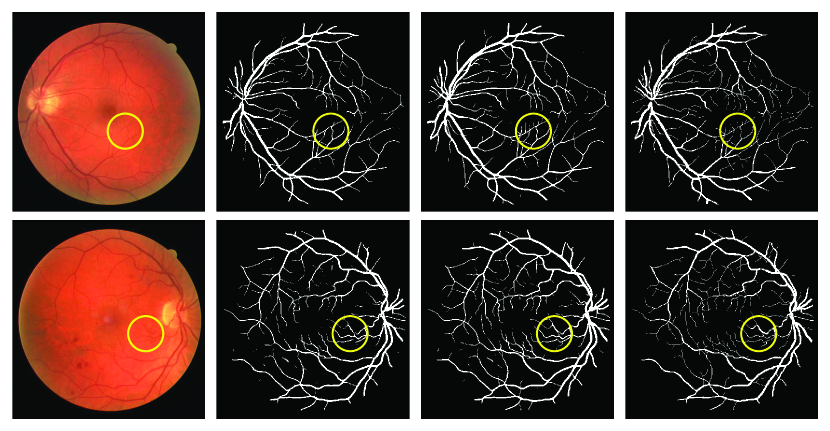

Figure 4: Two fundus images in the DRIVE database (1st column), the segmented results obtained by using U-Net (2nd column) and our proposed PC-Net (3rd column), and the ground truth (4th column).

Results on DRIVE database: Fig. 4 shows two fundus images in the DRIVE database, the segmented results obtained by using U-Net and our PC-Net, and the ground truth. It reveals that our PC-Net is able to detect most of thin vessels and maintain the complex spatial structures (highlighted in yellow circles).